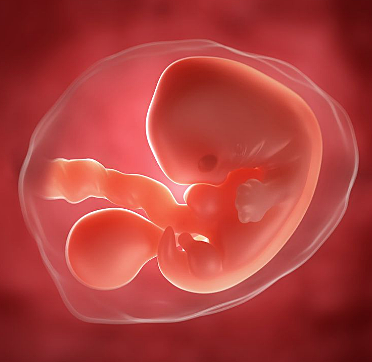

• Semana 3

Semana 3

En la semana 3 de embarazo empieza el proceso de gestación. Es la formación de capas germinales del embrión, denominadas también capas de tejidos primarios, las cuales son:

• Ectodermo: capa externa que envuelve al embrión.

• Mesodermo: capa de células que constituyen la parte superior del blastocito.

• Endodermo: capa de células más internas del conjunto embrionario.